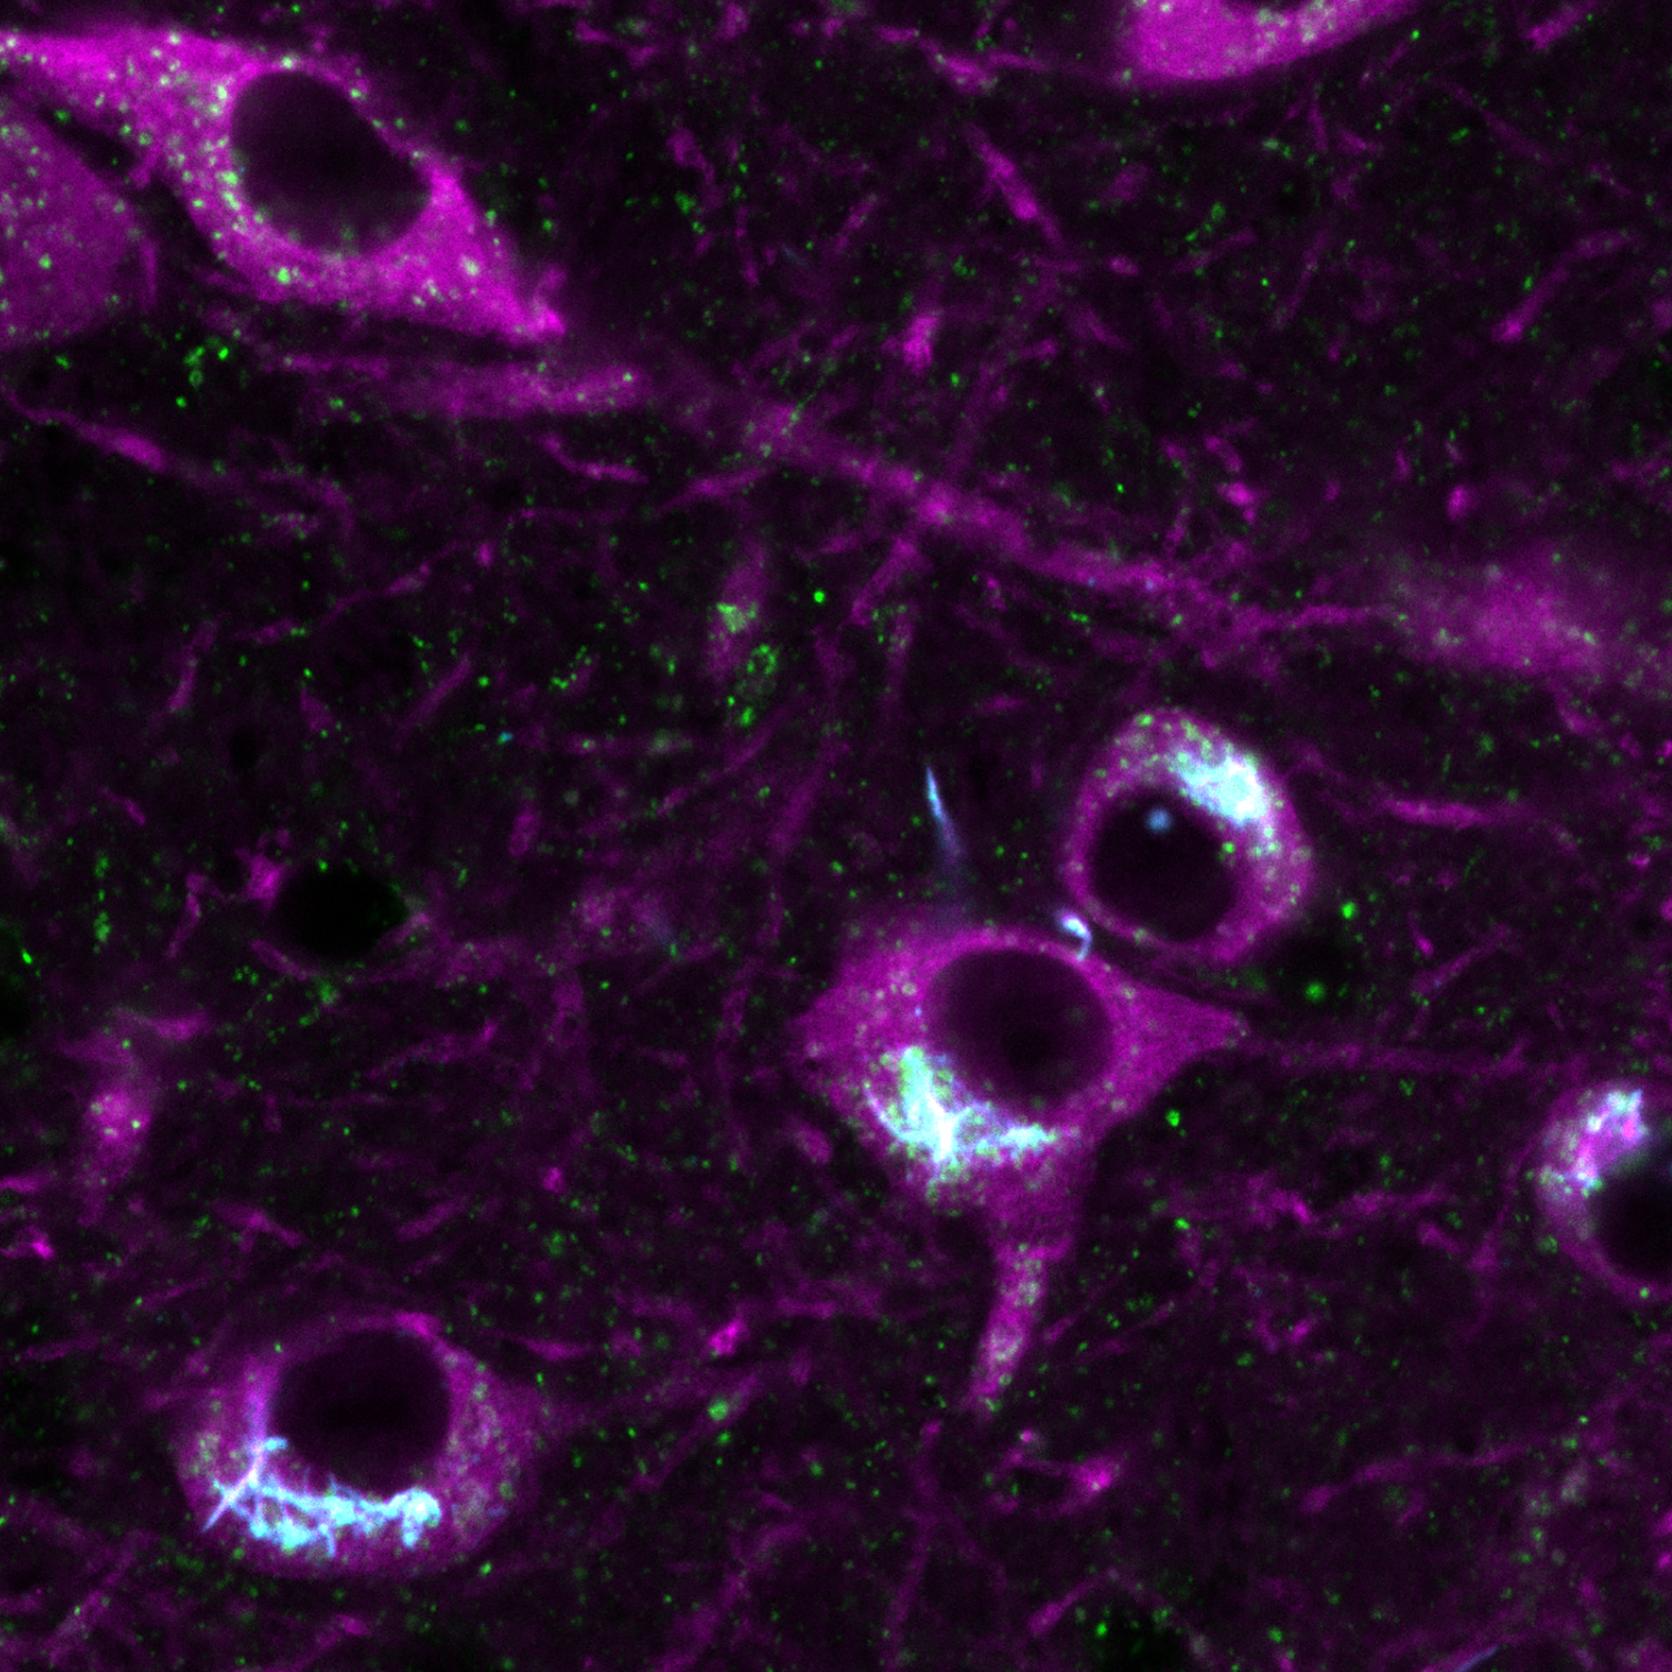

Dopamine neurons in the brain.

We are delighted to announce that the Brain Network Dynamics Unit has received Collaborative Award funding from Wellcome for a substantial multi-year research programme designed to advance the understanding of dopamine neuron dysfunction in Parkinson’s.

Professor Peter Magill, who will lead the Unit’s contribution to the new research programme, commented, “This Collaborative Award presents an exciting opportunity for Unit researchers to team up with other experts and tackle the science from different angles using complementary approaches. It is an excellent fit to the Unit’s wider strategy supporting both fundamental and translational neuroscience research. We look forward to working with our collaborators as we pursue our shared goal of defining why dopamine neurons are so vulnerable in Parkinson’s.”